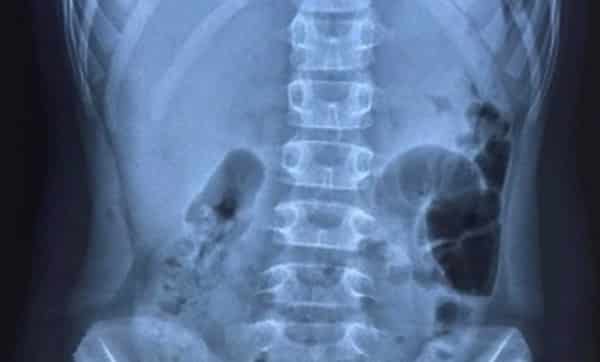

Hình ảnh chụp X-quang cho thấy bệnh nhi có liềm hơi dưới vòm hoành 2 bên, chẩn đoán thủng tạng rỗng. (Ảnh: benhvientreemhaiphong.vn)

Theo tin từ Bệnh viện Trẻ em Hải Phòng, ngày 22/2, các bác sĩ của bệnh viện đã hội chẩn từ xa một bệnh nhi 10 tuổi dương tính với SARS-CoV-2. Bệnh nhi bị đau bụng dữ dội vùng trên rốn kèm sốt, nôn 1 ngày; qua chụp Xquang, có hình ảnh liềm hơi dưới vòm hoành 2 bên , nghi ngờ thủng tạng rỗng. Bệnh nhi được yêu cầu chuyển gấp lên Bệnh viện Trẻ em Hải Phòng để điều trị.